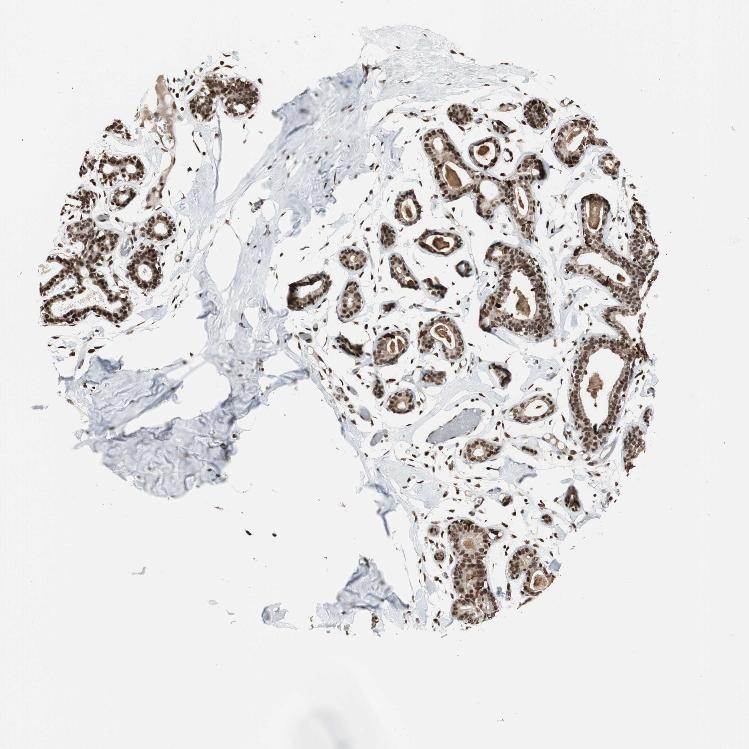

BREAST - Antibody stainingi

Antibody staining in the annotated cell types in the current human tissue is reported as not detected, low, medium, or high, based on conventional immunohistochemistry profiling in selected tissues. This score is based on the combination of the staining intensity and fraction of stained cells.

Each image is clickable and will lead to virtual microscopy that enables deeper exploration of all samples and also displays staining intensity scores, fraction scores and subcellular localization as well as patient and tissue information for each sample.

Antibody HPA006314Antibody HPA012010Antibody CAB011673

Adipocytes HighNot detectedNot detected

Glandular cells HighMediumMedium

Myoepithelial cells HighLowLow